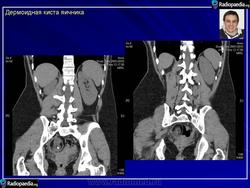

Зрелая тератома яичника.

Приложения:

101.pozhilye_kistoznoy_teratomy_yaichnika.jpg102.pozhilye_kistoznoy_teratomy_yaichnika.jpg103.pozhilye_kistoznoy_teratomy_yaichnika.jpg104.pozhilye_kistoznoy_teratomy_yaichnika.jpg